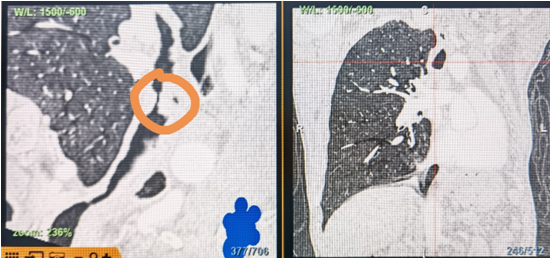

時間就是生命!了解患者病情后,歐陽海峰立刻啟動氣道梗阻緊急救治通道,協(xié)調(diào)院前轉運,急診快速入院流程。凌晨患者入院胸部CT顯示,現(xiàn)存唯一的呼吸通道在右主支氣管處,狹窄處僅約3毫米,患者命懸一線!

運用呼吸介入技術,軟硬鏡結合快速開通氣道,是患者目前唯一可行的治療方案,手術刻不容緩!但存在麻醉后氣道完全塌陷閉合、大出血、窒息等巨大風險?;颊叽饲敖舆B轉診3家醫(yī)院,均建議保守支持治療或轉院。歐陽海峰詳細了解患者病史,全面評估影像檢查結果后,決定盡快進行手術,組織醫(yī)護團隊對患者進行持續(xù)密切監(jiān)測,充分保障其術前安全。

患者入院第二天,在麻醉手術中心全力配合下,歐陽海峰帶領呼吸介入團隊,歷時40分鐘快速置入硬質支氣管鏡、鏟切腫瘤,并順利植入全覆膜TTS支氣管金屬支架。患者氣短癥狀即刻緩解,為患者贏得了寶貴的后續(xù)治療機會。